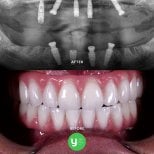

Зубные имплантаты All-on-6 предполагают установку 6 титановых имплантатов в верхнюю или нижнюю челюсть для поддержки целой дуги протезных зубов. Этот метод обеспечивает стабильное, долговечное и естественное решение для пациентов со значительной потерей зубов.

😊 Естественный внешний вид

Протезы изготавливаются под пациента, выглядят как натуральные зубы и восстанавливают уверенность в улыбке.